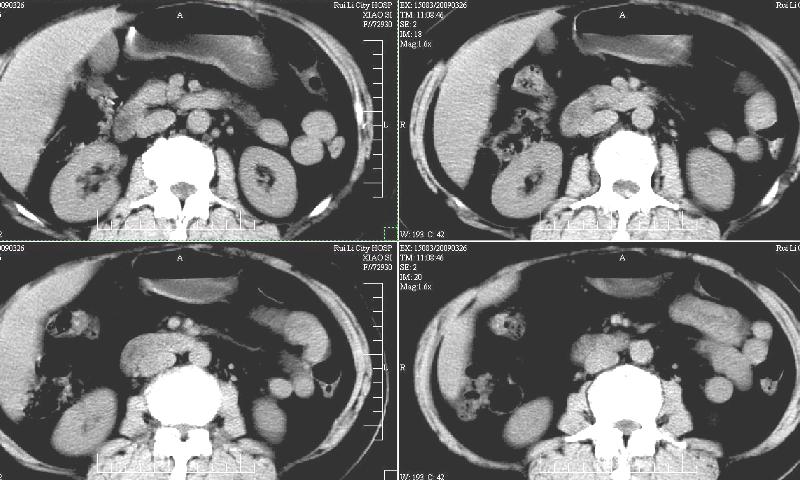

标题: CT19130:F,60岁。2008-10-17CT发现肝脏占位,现在复查! [打印本页]

标题: CT19130:F,60岁。2008-10-17CT发现肝脏占位,现在复查!

前次已经增强,所以这次没有增。ct:肝右叶平滑肌血管脂肪瘤治疗后复查,肿瘤大小同前或略有缩小。2、轻度脂肪肝。3、肝左叶小囊肿